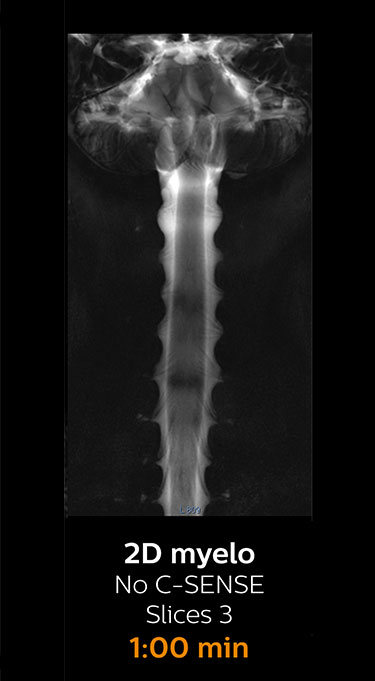

Fast MRI of lumbar spine

With Compressed SENSE, the scan time for the routine lumbar spine examination at KNC was reduced from 11:41 to 8:17 minutes,

which corresponds to 34% reduction.

MRI examination of lumbar spine with Compressed SENSE

MRI examination of the lumbar spine with Compressed SENSE

Ingenia 3.0T CX

Scan time 8:17 min. (was 11:41 min. without Compressed SENSE)